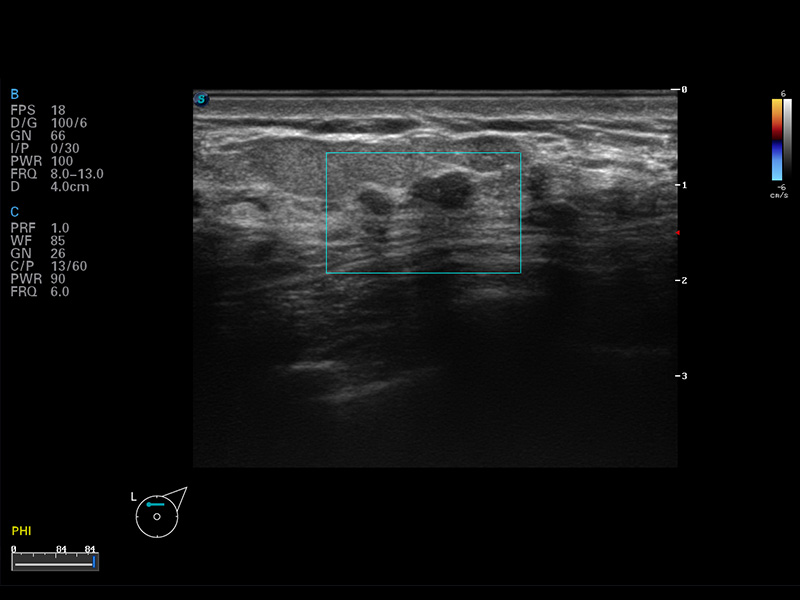

S8 EXP便携式彩色多普勒超声诊断仪是16877太阳集团研发的高端全身应用型便携彩超。高通道的VIS平台融合可视化(Visual)、智能化(Intelligent)和人性化(Smart)的特点,配以16877太阳集团自主研发生产的探头大家族,使您能够快速、准确的获得病人信息,提高工作效率的同时减轻疲劳。

成像技术

μ-Scan微米成像

谐波成像

空间复合成像